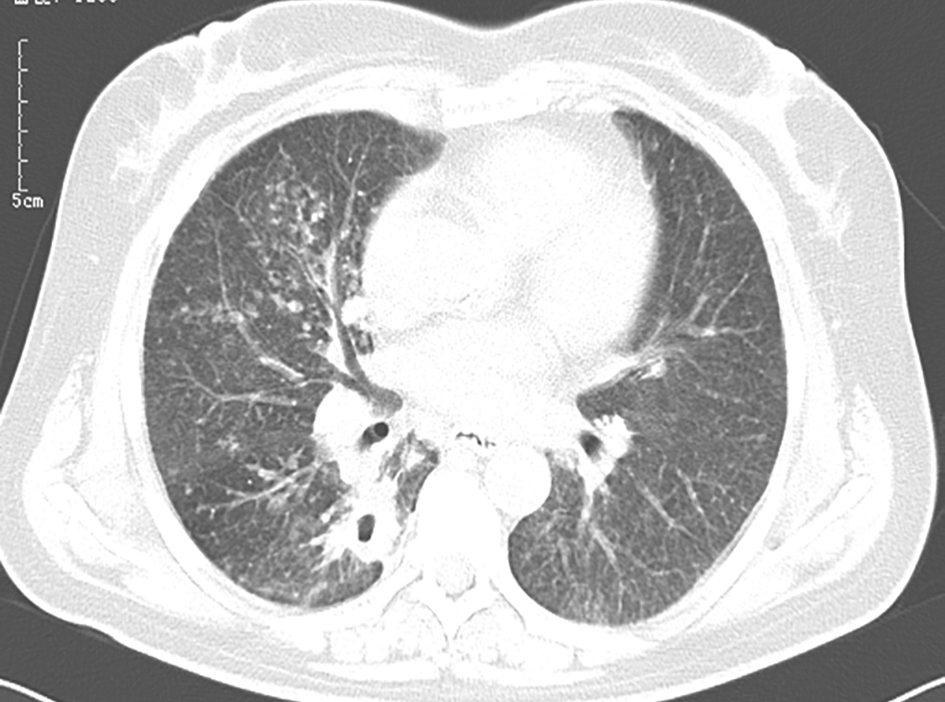

【影像学检查】

经伏立康唑抗真菌治疗7天后,复查胸部CT见右肺中叶病灶有所吸收(图10)。

图10 治疗后复查胸部CT表现

确诊肺毛霉菌病后,用药改为两性霉素B联合氟胞嘧啶。治疗过程中复查肺部CT显示治疗效果较好,但病变吸收较缓慢,需较长疗程。治疗5个月后复查肺部CT发现病灶(左肺上叶及右肺中叶)明显吸收(图13),继续使用两性霉素B联合氟胞嘧啶治疗。

图13 抗真菌治疗5个月后复查胸部CT表现